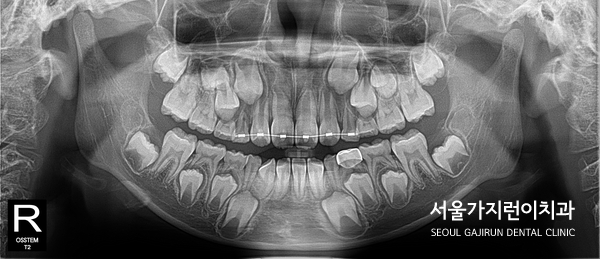

참고로 7살 어린이의 전후 사진을 비교해보면 교정을 시작한지 약 5개월만에 정상적으로 자리를 잡은 것을 확인할 수 있는데요. 앞니에 한정된 교정이었기 때문에 단기간에도 치료를 해볼 수 있습니다. 치아의 배열이 달라진 것을 파노라마 사진으로 확인이 가능한데요. 겉으로 보이지 않지만 혼합치열기의 환자분들은 숨은 치아들이 있기 때문에 초반에 맹출하는 치아들을 제대로 관리하지 못하면 영구치에도 영향을 미쳐 적절한 시기에 교정을 시작하는 게 좋습니다. 7살 교정? 너무 이른 거 아닌가요?에 대한 답변이 되셨을까요.